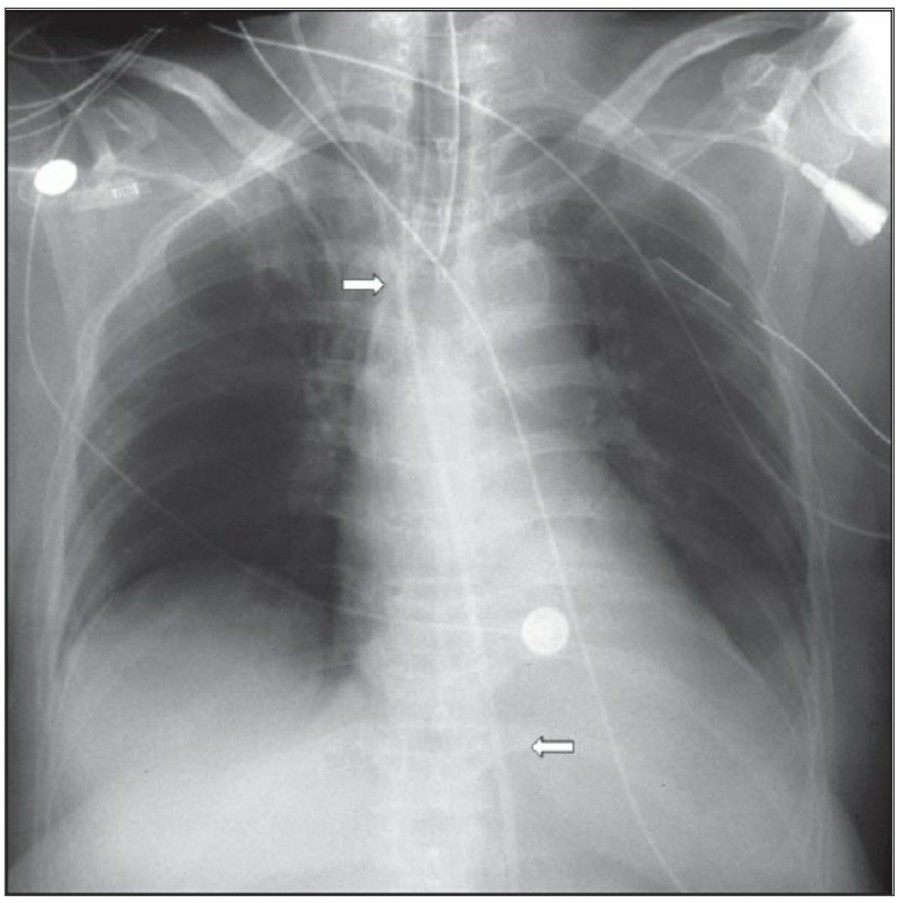

Pneumomediastinum

Pneumomediastinum은 mediastinum 안에 공기가 있는 경우를 일컬으며, intubation된 환자에서 구심적으로(centripetally) pulmonary interstitial dissection이 일어나는 경우와 관련이 있다.

또한 Mediastitnal air는 major airway 손상으로 인한 leakage나 retroperitoneum으로부터 fascial plane을 따른 air dissection에 의해 발생하기도 한다. Pneumomediastinum은 목까지 공기가 진행이 가능하고, pneumopericardium은 이와는 다르게 심장의 밑 부분으로 진행한다. Pneumomediastium은 일반적으로 무증상이지만, 간혹 청진 시 restrosternal crunch가 들릴 수 있다. Chest X ray상에서 공기가 major vessel 주변이나 SVC의 medial border, azygos vein에서 surrounding lucency로 보일 수 있다. 또한 aortic knuckle, descending aorta, pulmonary artery의 윤곽으로 나타날 수도 있다. Posteromedial pneumomediastinum은 주로 esophageal rupture의 결과로 나타날 수 있는데, praspinal costophrenic angle과 left diaphragm의 praietal pleural로 air dissection이 가능하다. 이 결과 V-sign of Naclerio라고 불리는 V-shaped lucency가 발생한다.

Pneumopericardium

Myocardium과 pericardium 사이에 공기가 존재하는 pneumopericardium은 pneumothorax의 합병증으로 발생 가능하지만 대부분은 심장 수술 후에 발견된다. Chest X ray 상에서 heart 주변으로 main pulmonary artery까지 진행된 lucent line으로 관찰된다. 공기는 cardiac shadow 아래에 모이는데 이는 continuous diaphragm sign으로 불리는, diaphragm 위의 midline을 건너는 소견이 나타난다.